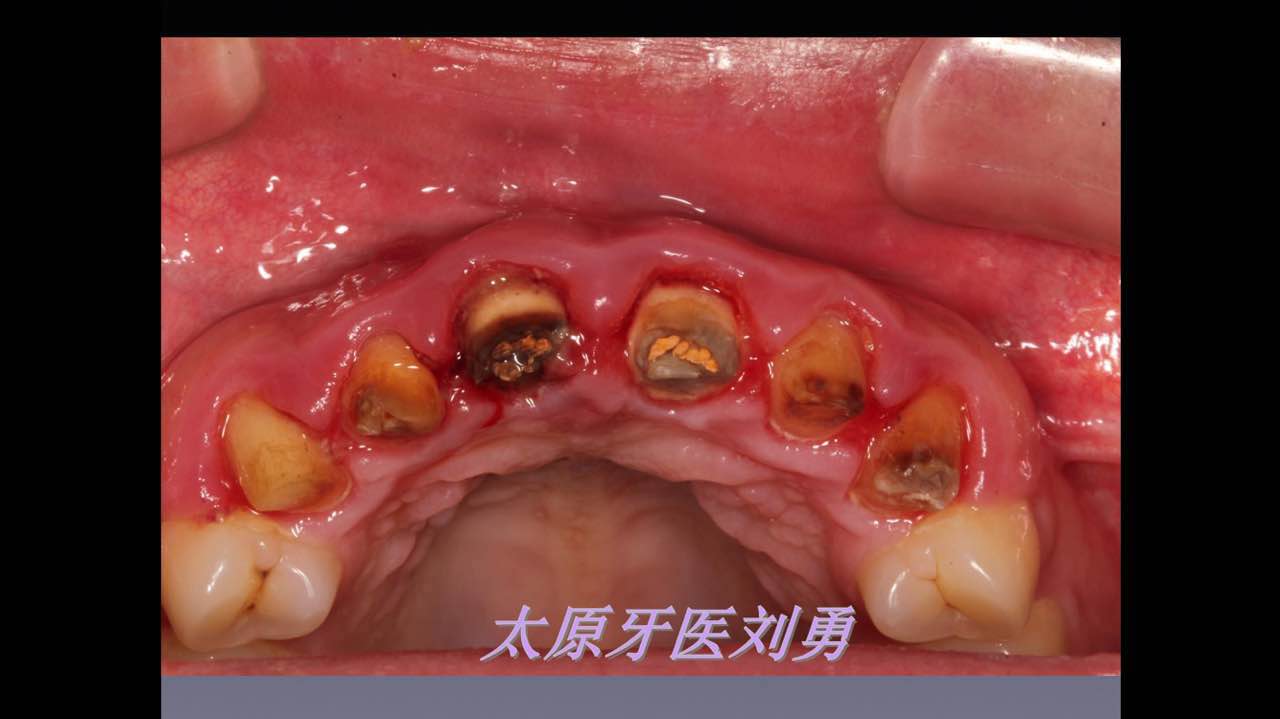

嚴(yán)重破壞生物學(xué)寬度,根尖瘺管,重行根管治療, 第一次冠延長建立唇腭側(cè)及鄰面BW,術(shù)后牙齦扇貝形差, 齦乳頭黑三角,再次行美學(xué)冠延長,建立牙齦扇貝形,手術(shù)免費, 患者因經(jīng)濟原因只能選擇鑄樁及鈷鉻合金烤瓷冠。終于完工